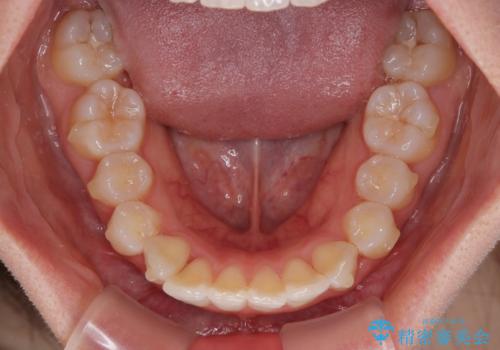

- 上の前歯の隙間を気にして来院された患者様です。

インビザラインにより、上下の歯列を側方に拡大しつつ、前歯の隙間を閉じていくこととしました。

隙間の原因は強い咬合力や舌の突出癖、小帯の異常付着などがありますが、舌のトレーニングをしっかりと行いながら、装着時間を遵守して装着していただいたおかげで、スムーズに治療を終えることができました。